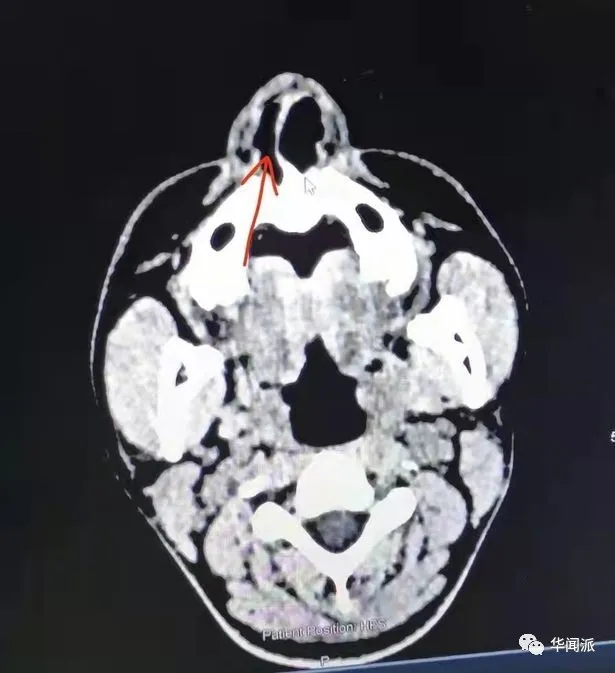

▲掃描顯示,Zhang先生因鼻骨和鼻中隔骨折需要手術**(圖****片來自Cambridgeshire Live)**